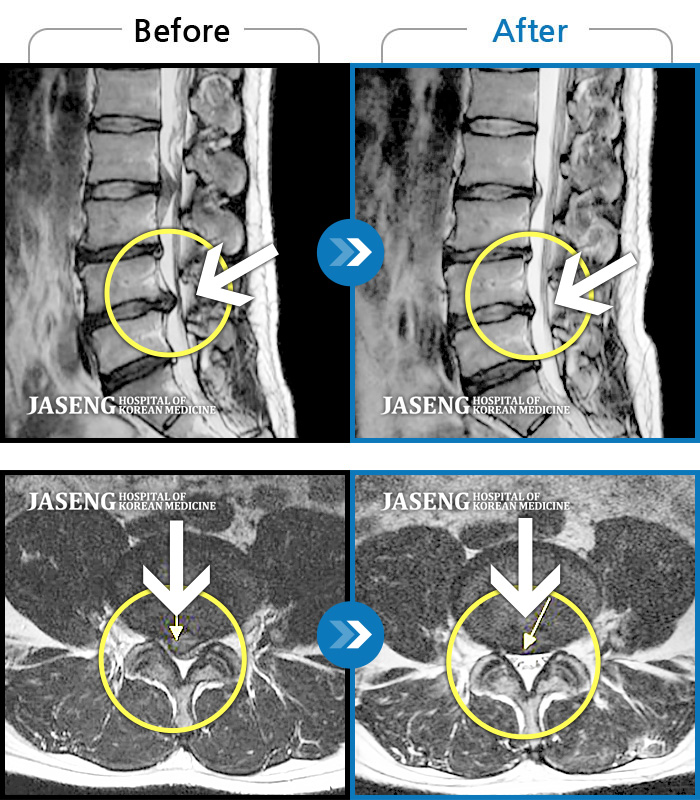

디스크와 협착이 심해 가는 대학병원마다 수술해도 예후가 좋지 않을거라 했었어요. 그게 3년 전이네요.. 5분도 못걸었을 만큼 허리, 다리 통증과 감각이상, 운동신경 손상 등 앞이 깜깜 했는데 꾸준히 다녔더니 분명 효과가 있습니다. 그사이 병가로 휴직했던 직장에도 복귀했구요. 희망의 끈을 놓지 않게 격려해주시고 치료해주신 박현민 원장님을 만났던게 신의한수 였던 것 같습니다. 마음 깊이 감사합니다~